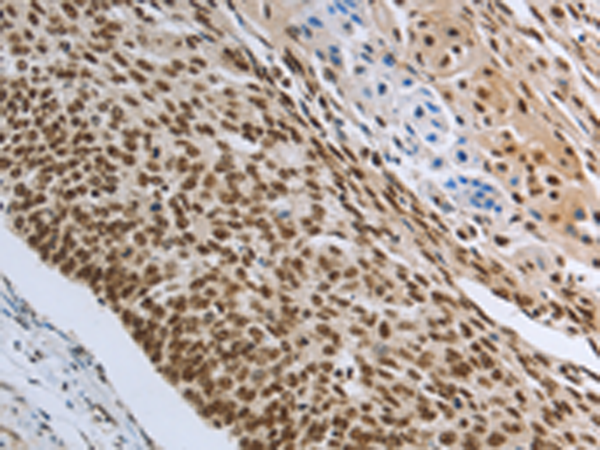

分类: 科研抗体货号: P11097别名: PRMT4应用: IHC反应种属: Human, Mouse, Rat